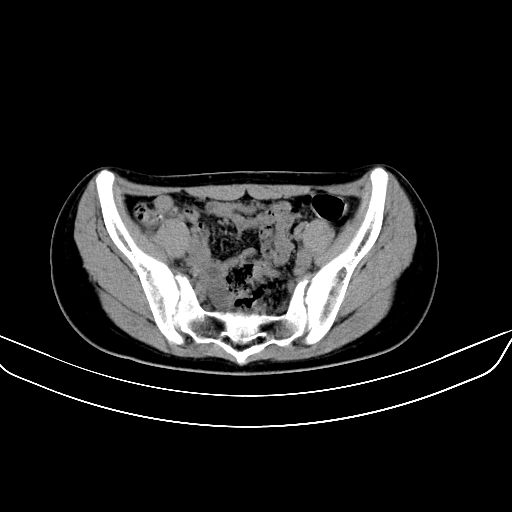

以下是引用zsl6918在2008-7-11 21:40:00的发言:[br]双侧骶髂关节骨质破坏以下三分之一为主,符合强直性脊柱炎表现

以下是引用zhangzhongshou在2008-7-11 21:41:00的发言:[br]患者是女性,hla-b27抗原(—),首先不太考虑强直性脊柱炎,建议查类风湿因子,骶髂关节改变考虑类风湿性关节炎可能性大,建议进一步检查。